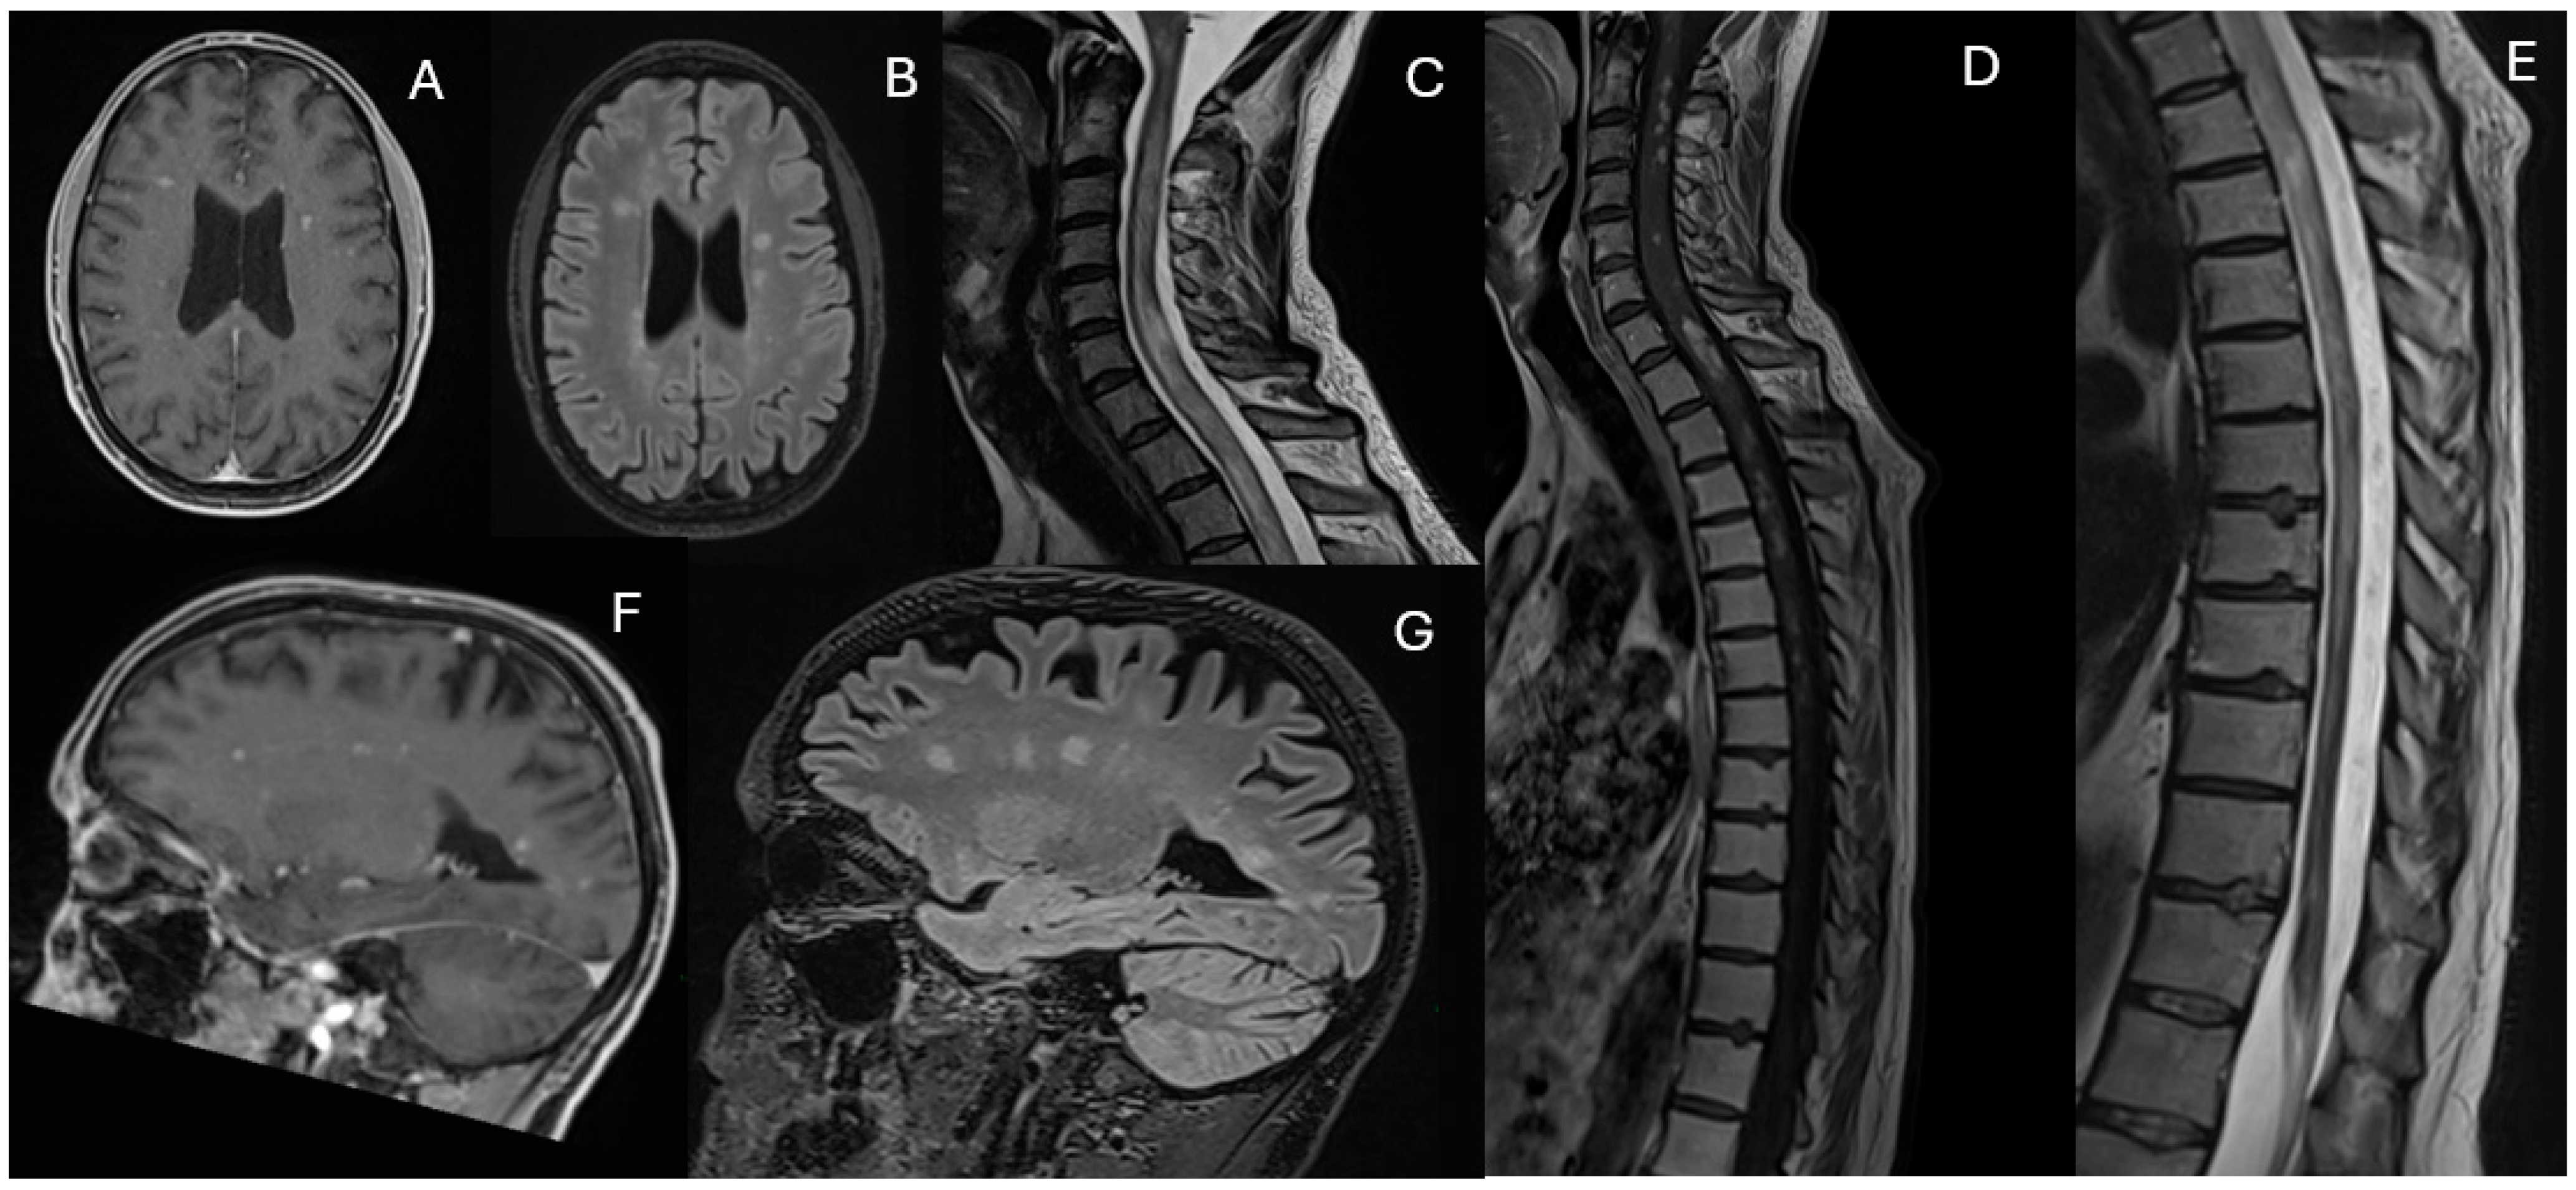

Magnetic Resonance Imaging (MRI) revealed multiple white matter lesions, hyperintense on FLAIR sequences and contrast-enhancing on T1-weighted images, with an asymmetric and periventricular distribution in the brain and spinal cord (Figure 1).

Figure 1. Contrast-enhanced T1-weighted (A,C,F,H), fluid-attenuated inversion recovery (FLAIR) (B,D,E) and STIR (G) images from the patient at baseline (October 2021). The images show multiple hyperintense FLAIR and contrast-enhancing white matter lesions with an asymmetric and periventricular distribution in the brain. Similar lesions are present in the spinal cord.